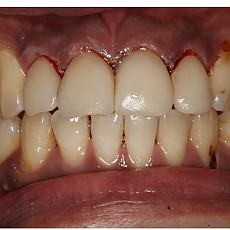

시술전후사진 12 페이지

Total 189건 12 페이지